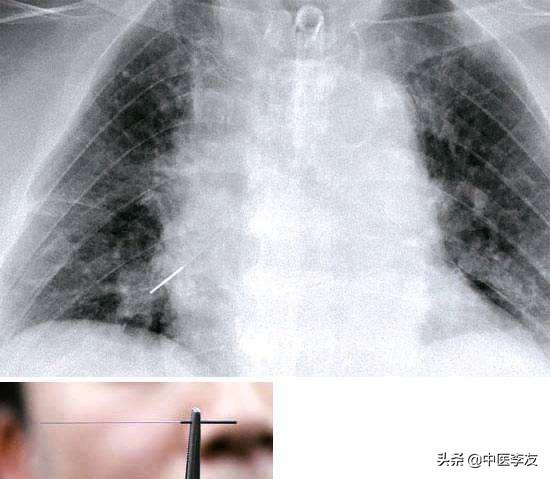

第4种是断针:断针就是指我们针灸的时候由于针具的质量问题,手法操作不当或者是病人扎下针以后,体位姿势变动幅度过大造成的针体断在输穴处的肌肉里面。

碰到这种现象,医生和患者都必须保持从容镇静。如果断端的针体露在皮肤之外,我们可以直接用医用钳子取出来;如果整体的残留端已经在人体皮肤之内看不到或够不着,必须要用x线定位结合外科手术取出;如果残留的针端刚好与皮肤平行,我们可以用食指与中指按压输血的两旁,轻轻的向下挤压肌肉,使残留体的针端整体露出皮肤之外,再用钳子夹住取出来。